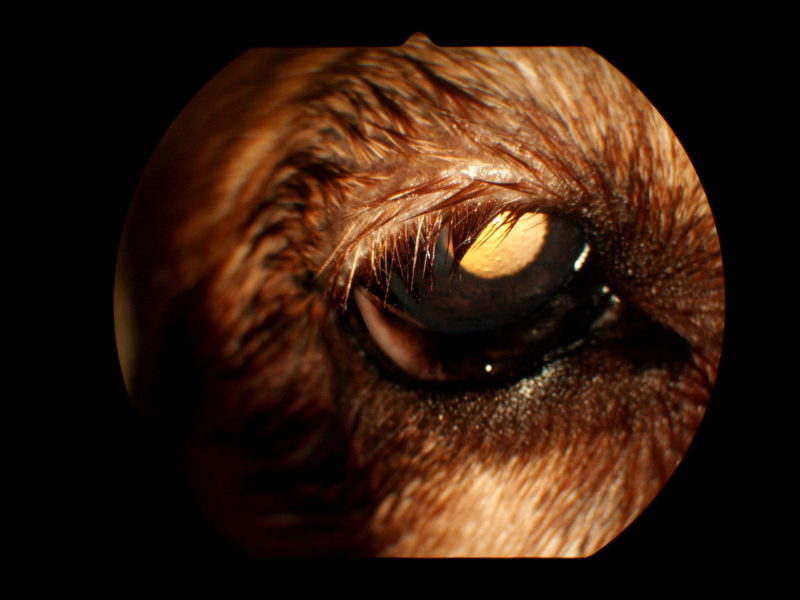

Die Ursache für diese Symptome ist eine multifaktorielle Lidfehlstellung bei „Murphy“. Beide Augen wiesen eine zu große Lidspalte (Makroblepharon) auf. Dadurch ergaben sich zum einen ein ungenügender Lidschluss mit hängenden Unterlidern und chronischer Reizung der Bindehaut und der Hornhaut. Zum anderen waren die Oberlider beidseits aufgrund einer fortgeschrittenen Bindegewebsschwäche auf beiden Seiten hängend und rechts zudem eingerollt. Dies führte rechts zu einer massiven Reizung der Hornhaut durch die Fellhaare (Trichiasisreizung, Abb. 1) mit einem sehr schmerzhaften Defekt in der Hornhaut (Ulkus korneae, Abb. 2). Diese Form des eingerollten oder hängenden Oberlides entsteht durch eine altersbedingte erworbene Bindegewebsschwäche.